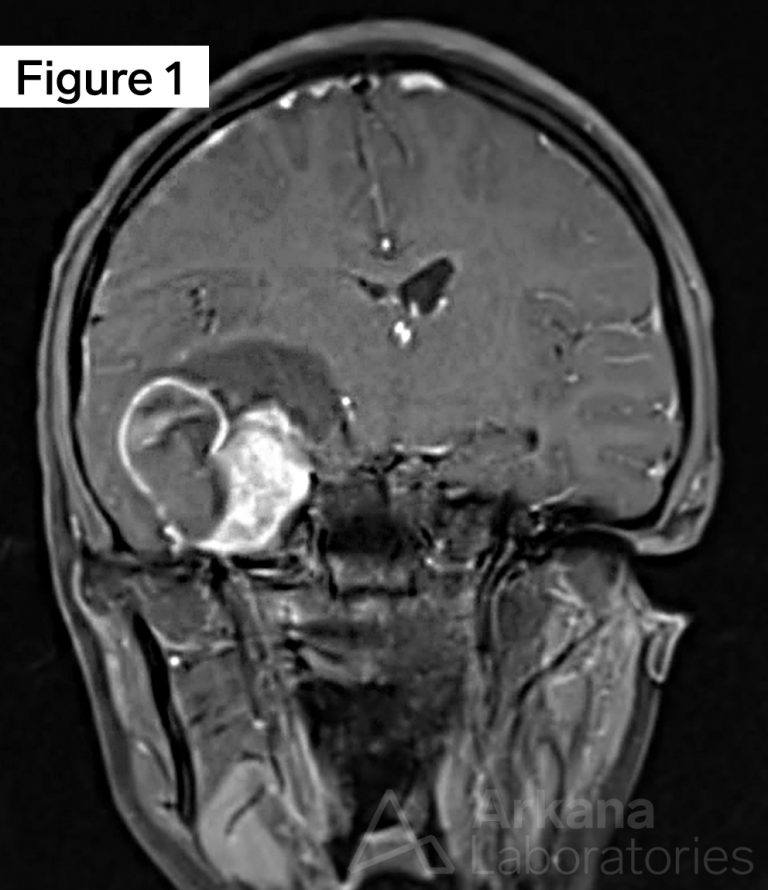

Ganglioglioma BRAF V600EMutated Neuro Notes Arkana Labs Braf Mutation Ganglioglioma brafv600 mutations are frequently found in several glioma subtypes, including pleomorphic xanthoastrocytoma. among ganglioglioma, the incidence of braf v600e mutations varied from 30 to 60% and the mutated protein seems to be predominantly localized to the neuronal. three gangliogliomas with braf p.v600e mutation had concurrent cdkn2a homozygous deletion and one additionally. national comprehensive cancer network guidelines. Braf Mutation Ganglioglioma.

Figure 1 from Personalized Treatment for a Patient With a BRAF V600E Braf Mutation Ganglioglioma as a who grade i tumor, the extent of surgical resection is the major. among ganglioglioma, the incidence of braf v600e mutations varied from 30 to 60% and the mutated protein seems to be predominantly localized to the neuronal. three gangliogliomas with braf p.v600e mutation had concurrent cdkn2a homozygous deletion and one additionally. brafv600 mutations are. Braf Mutation Ganglioglioma.